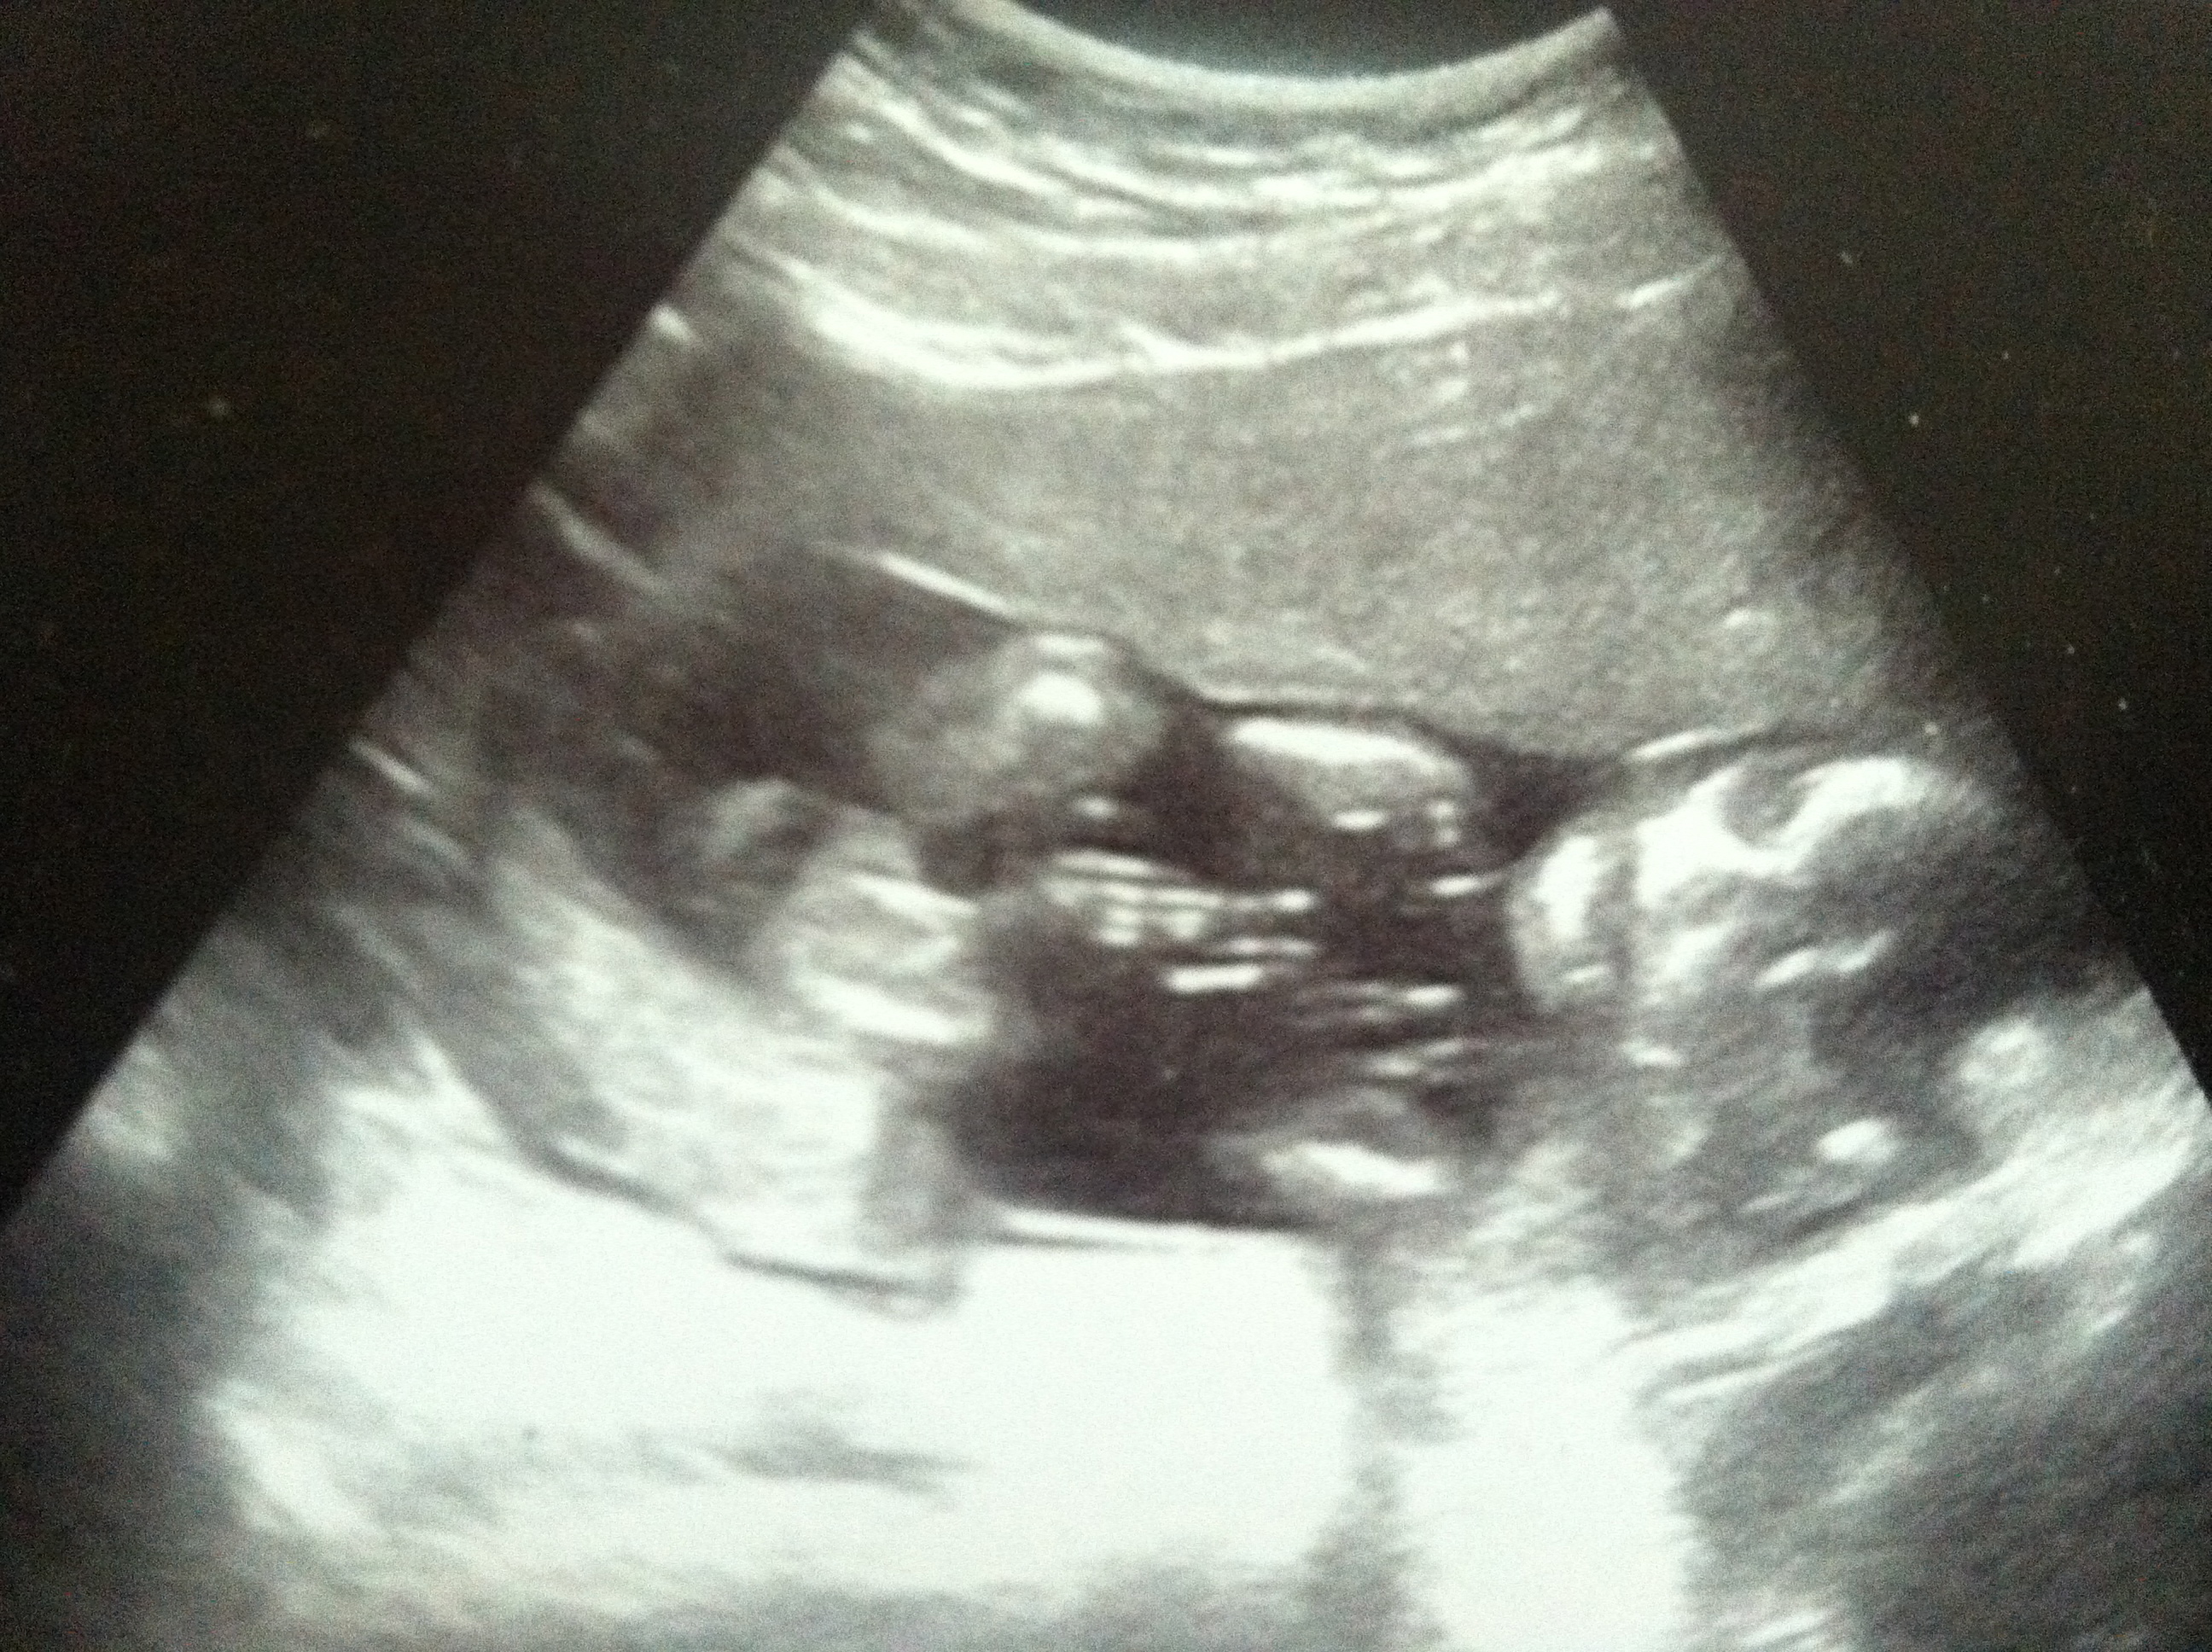

I'm 20 weeks today!!! It's also my 6 year anniversary at the daycare so it's a great day all around. I'm putting a bonus pic of my little guy from my a/s on Monday. We're still having a boy and those are his feet up by his face. The u/s tech said he was almost kissing his knee!